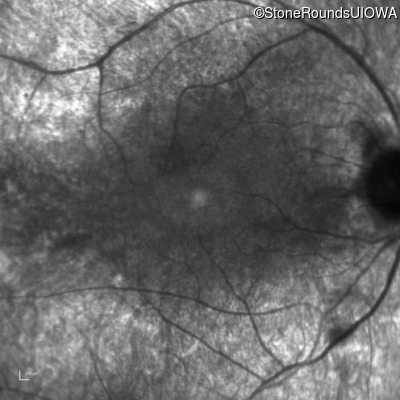

Infrared Fundus Photograph - Right - 20/40

Exemplar